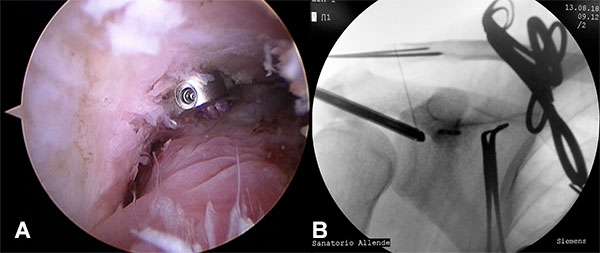

Con el paciente con bloqueo interescalénico y en posición de silla de playa con el brazo sin tracción en 10 a 20 grados de flexión y 20 a 30 grados de abducción, se introduce artroscopio por un portal posterior estándar y se realiza una artroscopia diagnostica en busca de lesiones asociadas. Se realiza un portal antero-inferior justo por encima del tendón del subescapular levemente más lateral de lo convencional con técnica de afuera-adentro y con dirección a la base de la coracoides, se realiza la colocación de cánula de 8,25 mm. Se realiza la apertura del intervalo de los rotador con shaver y electro bisturí artroscópico hasta la visualización de la punta y la base de la coracoides. Luego realizamos un nuevo portal percutáneo anterosuperolateral con técnica de afuera adentro y lo establecemos como nuevo portal de visión. Completamos la exposición de la base de la coracoides en la unión con la cara anterior del omoplato (fig. 1A) Se introduce el compás guía para AC TightRope o sistema DogBone por el portal antero inferior y se lo posiciona centrado en la coracoides a nivel de la unión de la base de la coracoides con la cara anterior del omoplato en 70 a 90 grados de angulación (fig. 1B). Se realiza un abordaje longitudinal de 2 a 3 cm a nivel del foco de fractura, se limpia foco de fractura, se reseca tejido interpuesto y se realiza la reducción de la fractura y fijación transitoria con clavijas de 1,6 mm, se controla reducción por radioscopia (fig. 2). La guía del compas es posicionada entre 25 y 30 mm medial a la articulación acromioclavicular y centrada en la clavícula para evitar lesionar la cortical anterior o posterior. Se realiza la perforación de la clavícula y la coracoides con drill pin canulado de 3 mm atravesando 4 corticales para pasar a través de la clavícula y coracoides visualizando posicionamiento por radioscopia, y control por artroscopia de la salida del drill pin en la base de la coracoides, se retira el pin del drill canulado y se introduce un alambre de nitinol que se recupera por el portal antero inferior (fig 3). Se retira el drill canulado dejando el alambre de nitinol. Si vamos a utilizar sistema AC TightRope debemos desmontar ambos botones del FiberWire y montar dos suturas FiberTape en el botón longitudinal para pasar a través del túnel coracoideo y clavicular solo los cuatro extremos suturas. Se montan los 4 extremos de las suturas FiberTape del implante subcoracoideo en el alambre de nitinol y se realiza el pasaje del mismo de distal a proximal (fig. 4). Bajo visión artroscópica directa se comprueba el pasaje y posicionamiento del botón subcoracoideo (fig. 5). Se realiza la reducción de la fractura aplicando presión inferior sobre el fragmento proximal de la fractura y contrapresión superior desde el codo para ayudar a reducir la fractura. Una vez reducida la fractura bajo control radioscópico se completa la fijación del botón clavicular del sistema AC TightRope o DogBone y con sutura FiberTape transósea se incorpora el fragmento distal de la fractura a la reconstrucción (fig. 6).

Figura 6: Fijación botón clavicular y sutura transosea del extremo distal de la fractura.